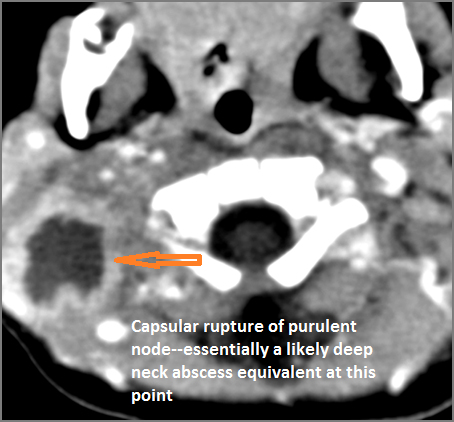

If there is suppurative cervical adenopathy the purulent material outside the lymph node(s) capsule(s).